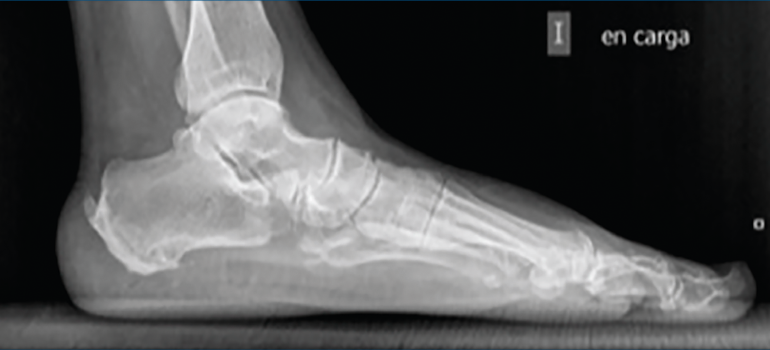

La OPC se realiza bajo anestesia general o regional junto con un bloqueo nervioso anestésico. Se debe tener en cuenta que este procedimiento es tan solo una parte de un conjunto de gestos quirúrgicos destinados a corregir la deformidad, fundamentalmente del pie cavo o pie plano (Figura 1).

Figura 1. Radiografía en carga prequirúrgica.